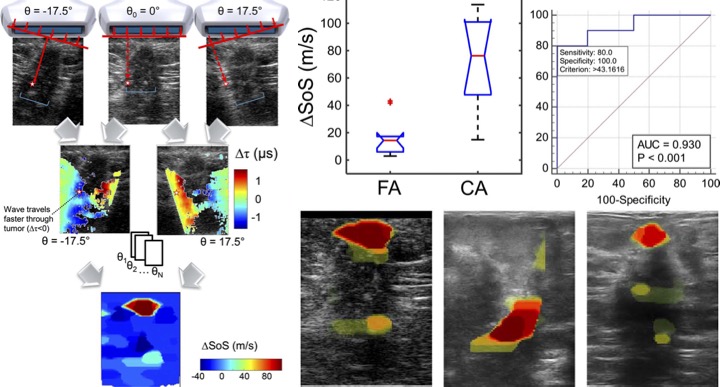

[2019] Lisa Ruby, Sergio J. Sanabria, Katharina Martini, Konstantin J. Dedes, Denise Vorburger, Ece Oezkan, Thomas Frauenfelder, Orcun Goksel, and Marga B. Rominger:

"Breast Cancer Assessment With Pulse-Echo Speed of Sound Ultrasound From Intrinsic Tissue Reflections: Proof-of-Concept",

Investigative Radiology 54(7):419-427, Jul 2019.

[2019] Lisa Ruby, Sergio J. Sanabria, Katharina Martini, Konstantin J. Dedes, Denise Vorburger, Ece Oezkan, Thomas Frauenfelder, Orcun Goksel, and Marga B. Rominger:

"Breast Cancer Assessment With Pulse-Echo Speed of Sound Ultrasound From Intrinsic Tissue Reflections: Proof-of-Concept",

Investigative Radiology 54(7):419-427, Jul 2019.

@article{Ruby_breast_19,

author = {Lisa Ruby and Sergio J. Sanabria and Katharina Martini and Konstantin J. Dedes and Denise Vorburger and Ece Oezkan and Thomas Frauenfelder and Orcun Goksel and Marga B. Rominger},

title = {Breast Cancer Assessment With Pulse-Echo Speed of Sound Ultrasound From Intrinsic Tissue Reflections: Proof-of-Concept},

journal = {Investigative Radiology},

year = {2019},

volume = {54},

number = {7},

pages = {419-427},

url = {https://www.zora.uzh.ch/id/eprint/170532/1/document.pdf},

doi = {10.1097/RLI.0000000000000553}

}